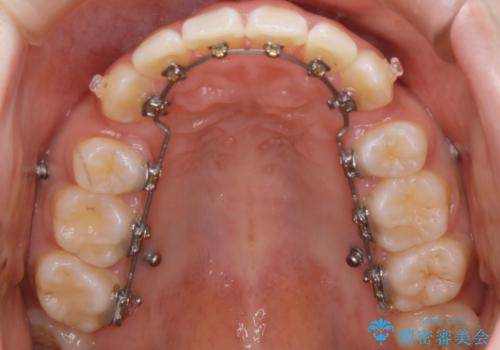

ハーフリンガル装置

ワイヤー矯正の中でも、上顎を裏側・下顎を表側に装置をつけて動かす方法をハーフリンガルといいます。

ハーフリンガルを選択すると、ワイヤー矯正の利点である抜歯ケースへの対応が可能な点と、表側の装置の欠点である装置が目立つという点をカバーして矯正治療を進めることができます。

表側の装置と違い、使えるワイヤーの種類に制限があり平均治療期間が長くなりやすい点、装置の作製自体の金額が掛かることから費用面で表側装置よりも高額になるという点はマイナスポイントであるといえますが、しっかりと口元を下げたり、噛み合わせの構築を行うことは遜色なく行えるため人気のある装置となっております。